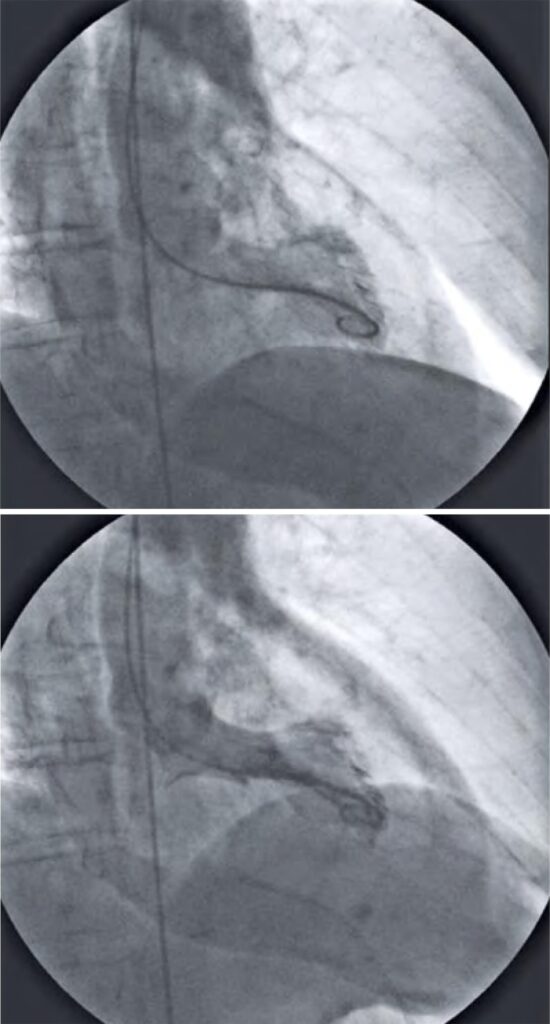

Figura 3

Ventriculografia esquerda em sístole com presença de ruptura da parede livre e tamponamento cardíaco.